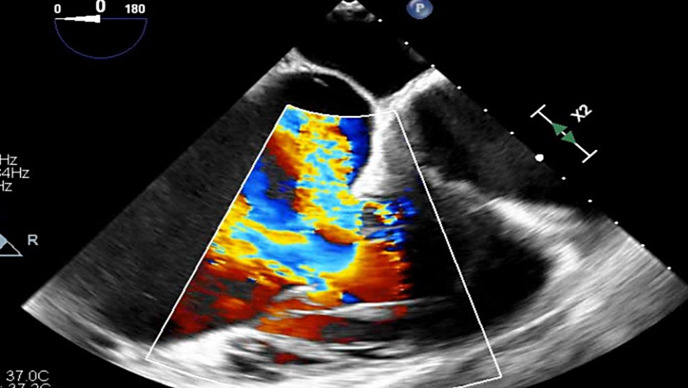

导言:迄今为止,还没有具体的证据或标准来选择肺动脉高压和严重三尖瓣关闭不全的患者,以启动三尖瓣瓣膜病变的矫正治疗。三尖瓣反流是与肺动脉高压患者死亡率无关的风险标志。手术成功的关键因素无疑是找到选择患者的参数,从而避免徒劳无功。方法:从最初的 271 名患者中筛选出最后的 123 名患者,这些患者均经导管检查确诊为毛细血管前 PH,并经超声心动图检查确诊为三尖瓣反流。根据《2022 年肺动脉高压指南》,患者被分为 1 组和 2 组。不排除右向左分流的患者。结果 在重度毛细血管前 PH 患者中,sPAP/PAAT 比值接近 1(0.89± 0.43),而在轻度毛细血管前 PH 患者或毛细血管后组患者中,sPAP/PAAT 比值要低很多(0.47±0.20)p<0.001。死亡患者的 sPAP/PAAT 平均值为 0.76。61.70%的死亡患者(68 例中的 42 例)有严重的三尖瓣反流。结论 在我们的研究中,严重三尖瓣反流死亡患者的平均 sPAP/PAAT 比值为 0.76 mmHg/ms,尽管如此,这一知识仍有潜在用途,但不足以在充分知情的情况下确定是否有资格进行瓣膜介入治疗,这需要具体的三尖瓣反流相关数据。

Results: In patients with severe precapillary PH, the sPAP/PAAT ratio was close to 1 (0.89 ± 0.43), while in patients with mild precapillary PH or in the postcapillary group, the sPAP/PAAT ratio was considerably lower (0.47 ± 0.20, p < 0.001). The average sPAP/PAAT of deceased patients was 0.76. Among the 68 deceased patients, 42 (61.70%) had severe tricuspid regurgitation.